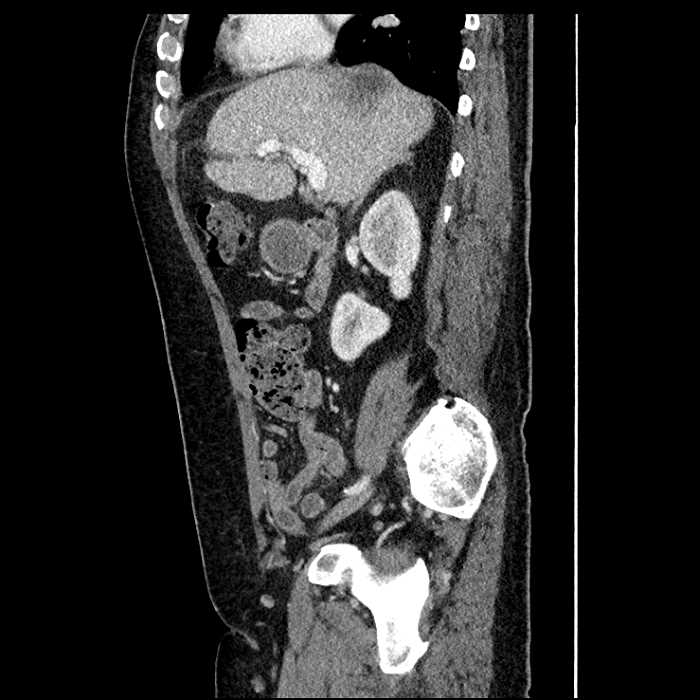

• Large fluid density structure in hepatic segments 7 and 8 measuring 10 x 7 x 7 cm with internal septation and circumferential ill-defined low density compatible with edema

• Peripherally enhancing subcapsular collections along the anterior margin of the left hepatic lobe measuring 3 x 1 cm and 2 x 1 cm

Acute sigmoid diverticulitis complicated by a small contained perforation and a large abscess in the right hepatic lobe. Additional small subcapsular abscesses along the anterior margin of the left hepatic lobe.

• The classic CT imaging appearance is a double target sign with internal low density surrounded by an internal enhancing rim (capsule) and a low density external rim (edema)

Hepatic abscess showing the double target sign with low density internally surrounded by a thin inner enhancing rim (red arrow) and ill-defined outer low density rim (yellow arrow). Blue arrow indicates an internal septation. Red arrows: additional smaller subcapsular abscesses. Red arrow: focal contained perforation associated with diverticulitis.